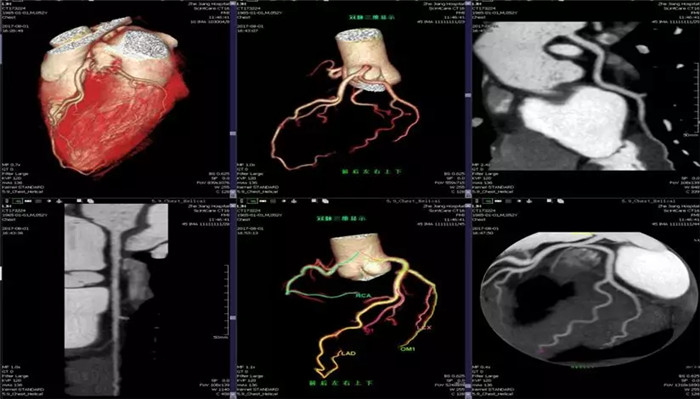

·心臟掃描應用

·全面臨床功能